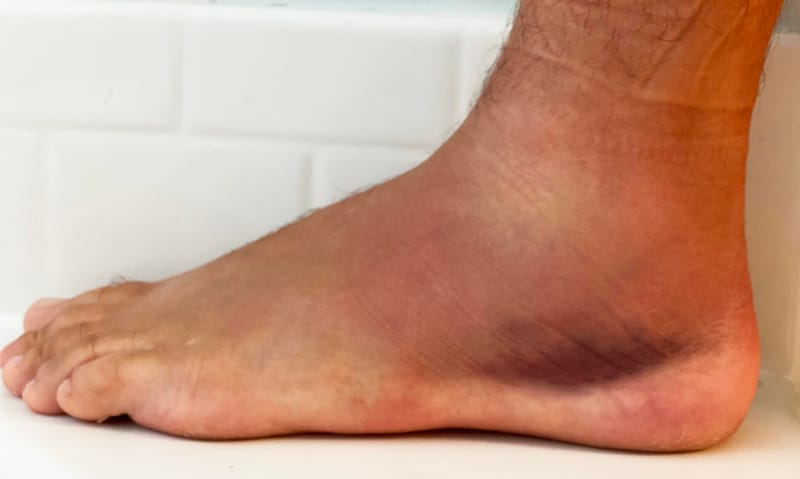

נקע בקרסול שלא מחלים